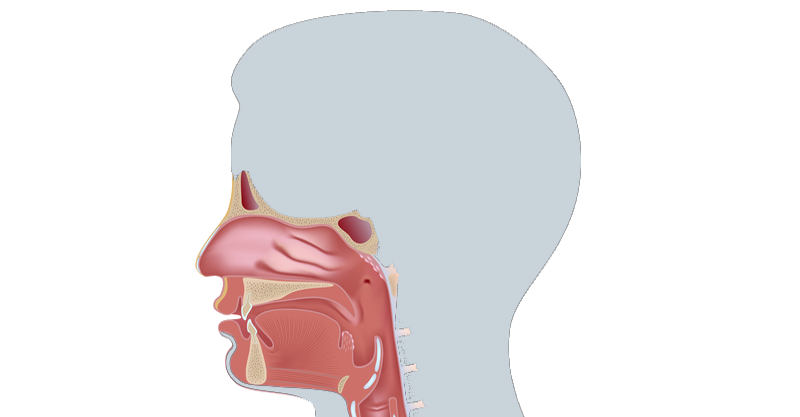

Верхние дыхательные пути: нос, околоносовые пазухи и полость рта и горла

Заболевания: аллергический ринит - - - пациент с трахеостомой